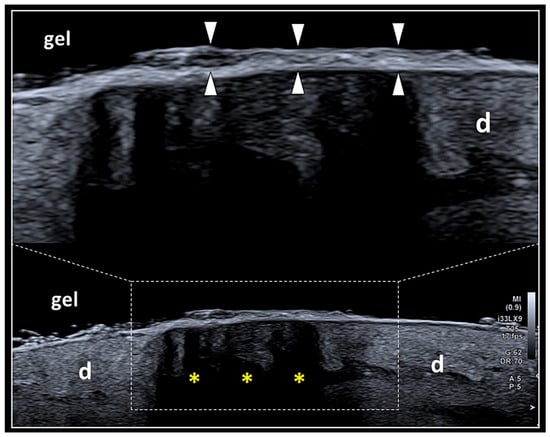

In the early phase of the healing process of skin wounds (7–12 days), the US examination should be avoided due to two main issues: the potential infectious risk related to the discontinuity of the epidermis and the so-called “deep masking effect”. The latter is a technical pitfall related to the massive thickening of the stratum corneum of the epidermis, which highly reflects the US beam preventing the visualization of the deep layers (Figure 3) [26]. It can be considered quite similar to the classical artifact of the posterior acoustic shadowing, commonly generated by hyper-reflective surfaces of the human body, e.g., the cortical bone or calcific deposits [27]. In this case, a practical trick is represented by the slight shift/tilt of the transducer to orient the US beam through the lateral aspect of the scar, circumventing the acoustic shadowing and improving the visibility of the deep tissues. Progressively, in the sub-acute (>15 days) or chronic (>30 days) phase of the healing process of skin wounds, the thickness of the stratum corneum and the spatial arrangement of the keratin laminae cover the scar change, allowing the US beam to penetrate toward the deeper tissue planes.

Figure 3.

The “deep masking effect”. Massive deposition of keratin laminae over the surface of the epidermis (white arrowheads) may generate a hyper-reflective interface reducing the penetration of the US beam within the deep layers and with the development of dark shadows (yellow asterisks) that mask the inner echotexture of the dermis (d). The “deep masking effect” can be physically considered very similar to the artifact of partial acoustic shadowing.